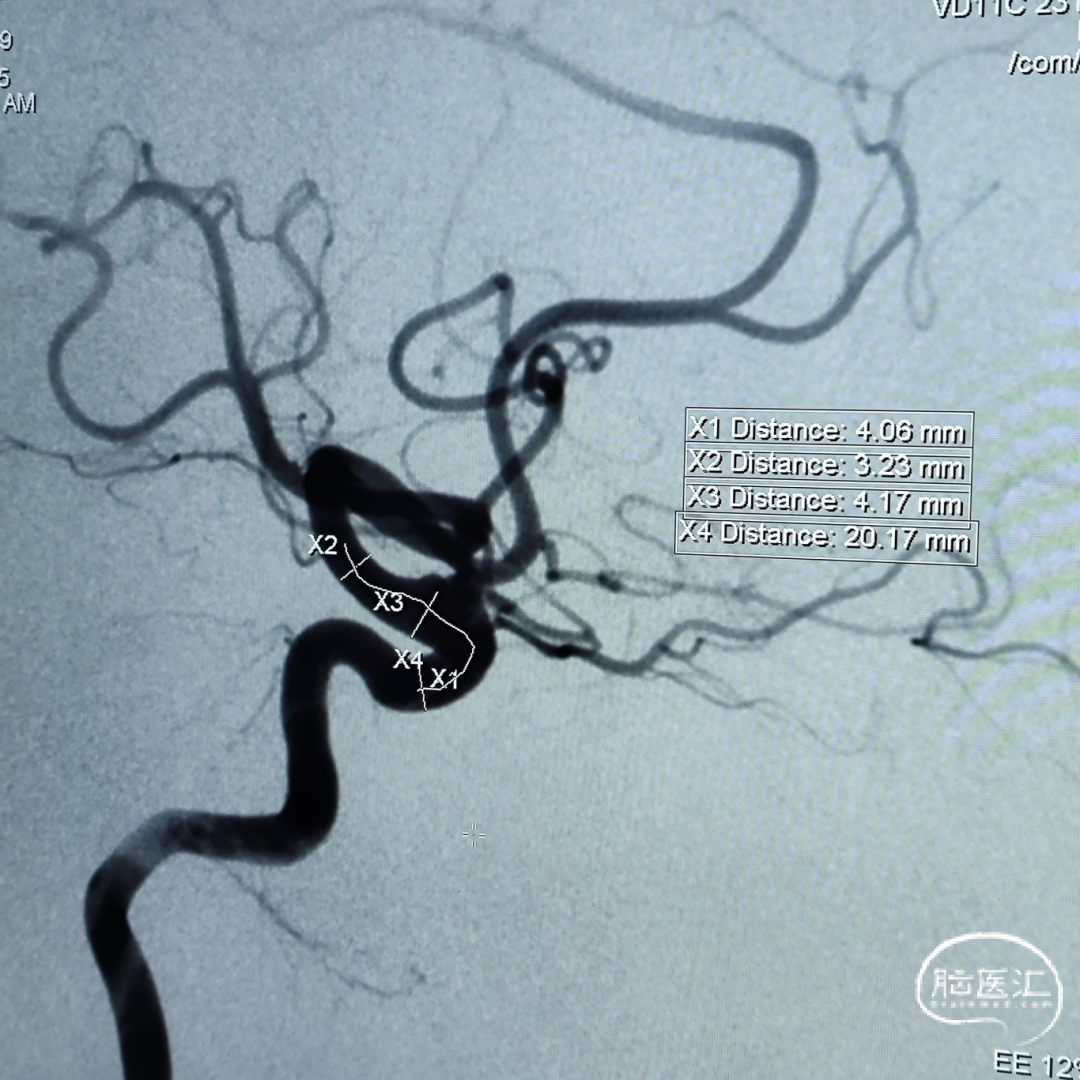

盖延廷教授病例分享一:左侧颈内动脉多发动脉瘤

患者:女性,55岁。

主诉:头疼,检查发现动脉瘤8月余。

入院查体:颅内多发动脉瘤。

术前诊断:

左侧颈内动脉:

远端锚定点脉前起始近端;近端锚定点海绵窦段。

载瘤动脉远端血管直径:3.23 mm

载瘤动脉近端血管直径:4.17 mm

选用4.25mm*25mm 强易达(Choydar)密网支架。